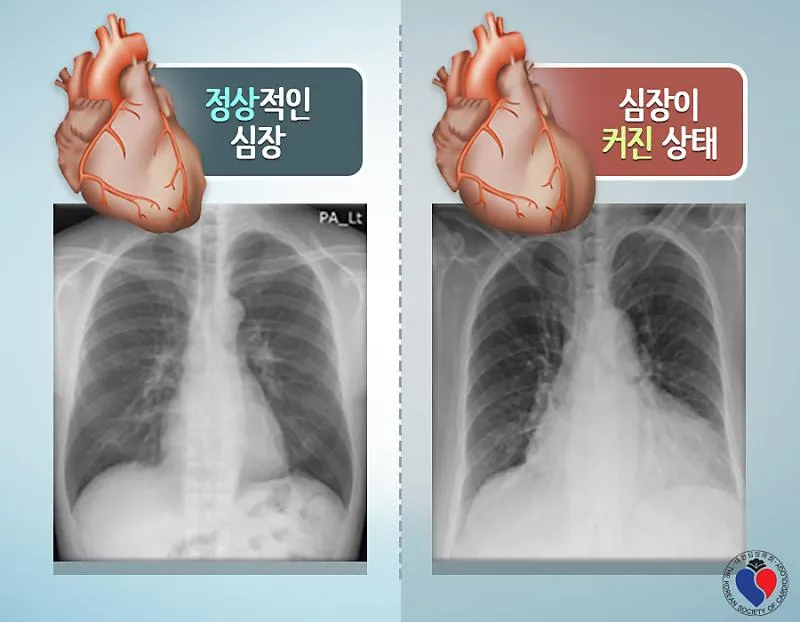

1. 심장 관련 원인

- 부정맥: 정상 심박수 범위 60-100회/분 이탈

- 심장 판막 이상: 증상 발현 시 심박수 변동 20% 이상

- 빈맥증: 휴식 시에도 심박수 100회/분 이상

- 서맥증: 심박수 60회/분 이하로 저하